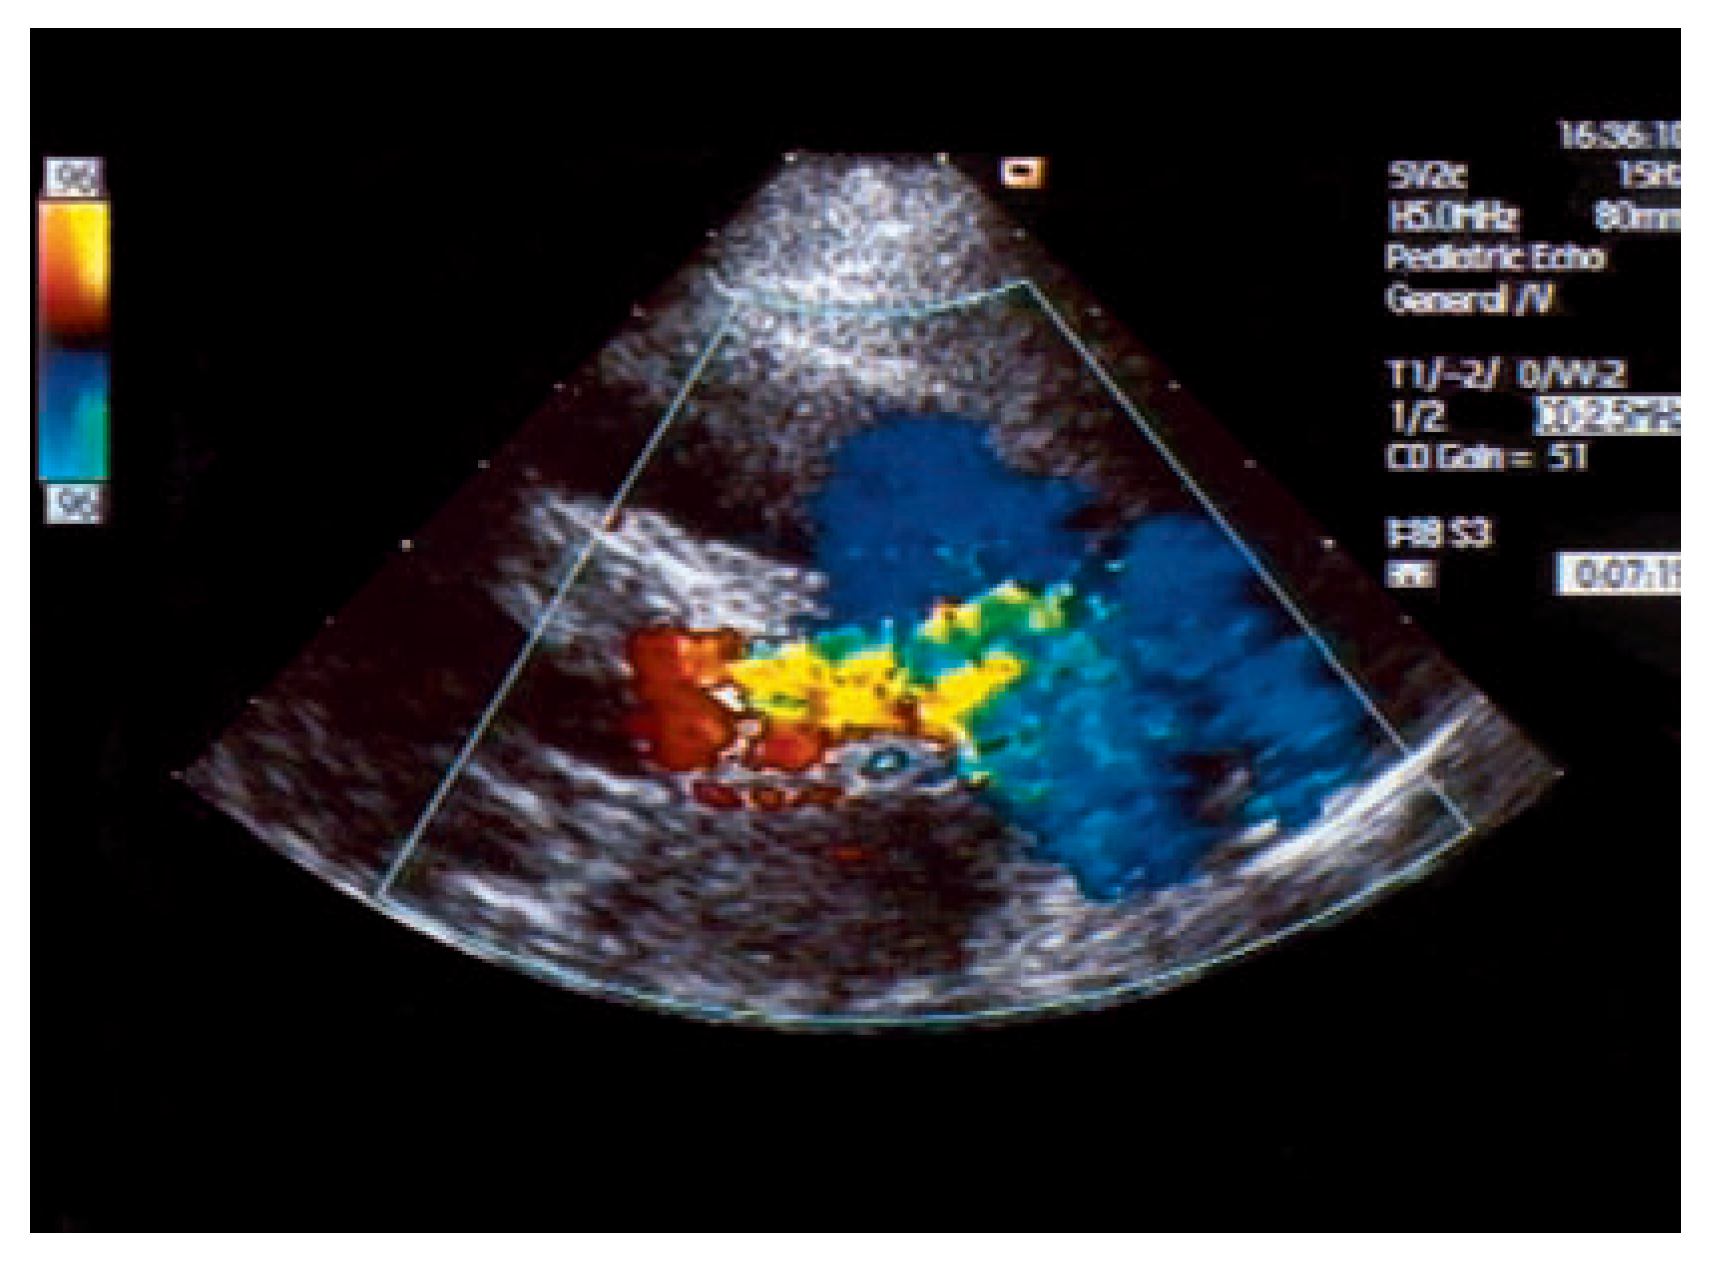

Asymptomatic Bland-White-Garland Syndrome in a 13-Year-Old Girl

Case report